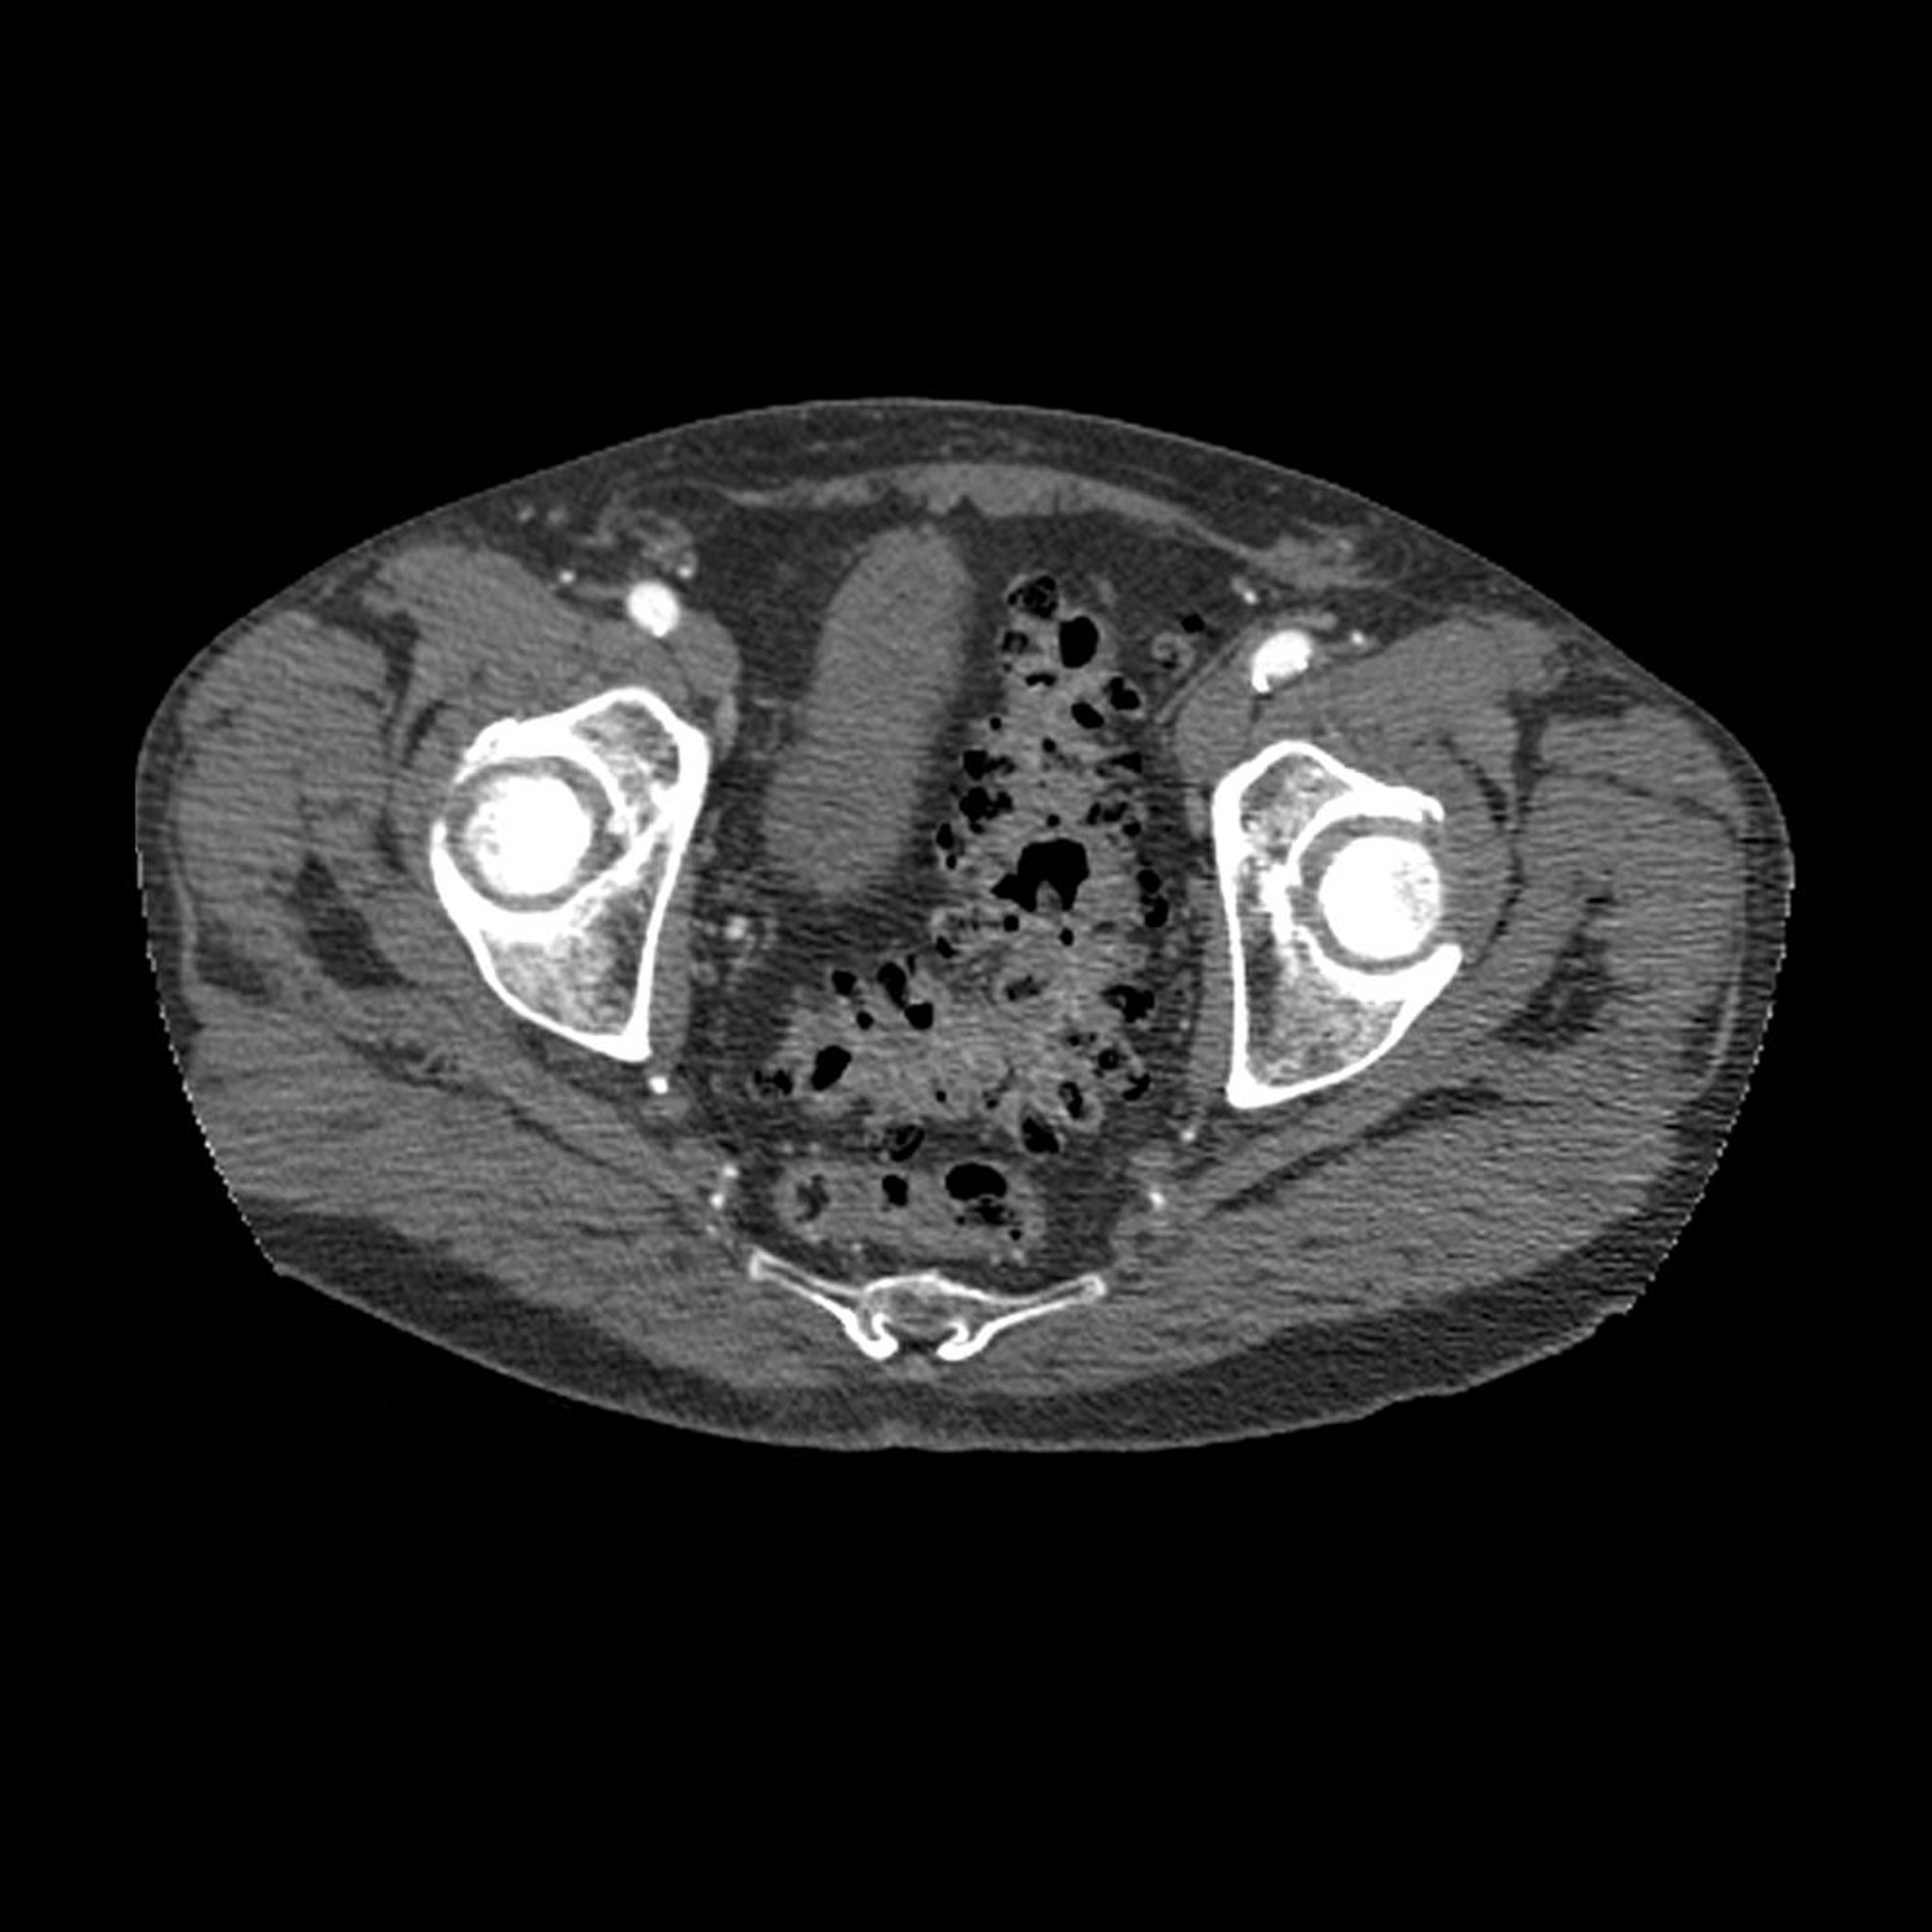

Bệnh túi thừa (chụp CT)

Hình ảnh CT mặt phẳng cắt ngang theo trục qua khung chậu cho thấy dấu hiệu điển hình của bệnh túi thừa (vùng tối trên thành đại tràng sigma).